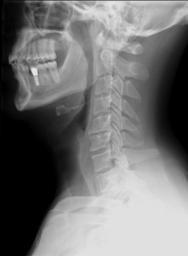

MAKE A MEME View Large Image Cervical Xray Lateral View.jpg en X-ray of cervical spine neck lateral side view This series of x-rays were part of pre-surgical evaluation to help identify spinal instability Patient is a 37 year old male with a history of multiple neck ...

Keywords: Cervical Xray Lateral View.jpg en X-ray of cervical spine neck lateral side view This series of x-rays were part of pre-surgical evaluation to help identify spinal instability Patient is a 37 year old male with a history of multiple neck traumas with pain and muscle spasms and dental implant in lower jaw Excerpt from radiologist's report FINDINGS Five views of the cervical spine including flexion and extension were performed There is no evidence of fracture bone destruction or malalignment There are degenerative bone and is changes at C5-6 There is no evidence of cervical instability on the flexion and extension views The facet joints are well aligned Bony spurring is narrowing the C5-6 neural foramina bilaterally IMPRESSION Degenerative changes at C5-6 No evidence of instability Ragioagraphie aux raysons X du rachis cervical cou vue latérale côté Cette série de radiographies faisaient partie de l'évaluation pré-chirurgicale pour aider à identifier une instabilité vertébrale Le patient est un homme de 37 ans ayant des antécédents de traumatismes multiples cou avec des spasmes et des douleurs musculaires et implant dentaire à la mâchoire inférieure Extrait du rapport du radiologiste RÉSULTATS Cinq vues de la partie cervicale de la colonne vertébrale ont été faites dont en flexion et en extension Il n'y a pas de signe de fracture de destruction osseuse ni de défaut d'alignement On observe un phénomène de gégénérescence osseuse des changements en C5-6 Il n'existe aucune preuve de l'instabilité du cou sur les radios montrant la flexion et l'extension Les facettes articulaires sont bien alignés Bony spurring is narrowing the C5-6 neural foramina bilaterally IMPRESSION Changements dégénératifs eu C5-6 Aucune preuve d'instabilité own medical image work for hire Stillwaterising 2010-04 thumbnail left thumbnail left Magnification 0 4x converted from lossy DICOM file Cc-zero Lateral X-rays of the neck with decreased lordosis Dicom Human anatomy cervical vertebrae